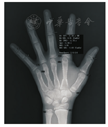

本研究采用的是自动骨龄评估软件BoneXpert 2.0版(Vi-siana,Denmark,http://www.BoneXpert.com)。在取得BoneXpert软件所有者Thodberg教授授权后,在科室PACS系统中安装了该软件。使用时只需将待评估的X线片(DICOM格式)传入该软件,其可自动获取PACS中待评估对象的性别、年龄、出生日期、摄片日期等信息,10~20 s便可在同一界面中给出另一张有骨龄评估结果的X线片,右上角显示了最终骨龄评估结果,见图1。

BoneXpert软件评估骨龄过程共分3步:第1步,以始于1998年的一种有效的图像处理技术即主动外观模型(AAM)为基础,选取1、3、5指骨,1~5掌骨及尺桡骨共15块骨头,通过识别每块骨头的形状、密度及主要成分的质地重建骨头的边缘。在这过程中可以同时评判骨头形态是否正常,不正常的骨头及摆放位置不正的图片将被自动拒绝;第2步,分别评估除2、4掌骨外其余13块骨头的成熟程度,即固有骨龄(2、4掌骨仅用于评估骨骼健康指数,即BHI),若评估结果与所有骨头平均值相差大于2.4岁,该骨头将不被接受,且最终接受骨头少于8块,那么将无法评估出该样本骨龄;第3步,将固有骨龄转化为GP骨龄及TW3骨龄,GP骨龄即为所有骨头骨龄的平均值,而TW3骨龄则是尺桡骨分别占20%比例,其余各骨平分剩余百分比。由于在日常工作中并未使用TW3骨龄评分法,因此在本研究暂时没有涉及TW3骨龄这一内容。此外,在初次评估后1周,简单随机法随机抽取40张X线片,重新用BoneXpert软件进行评估,并用秒表同时记录评估过程单位耗时。